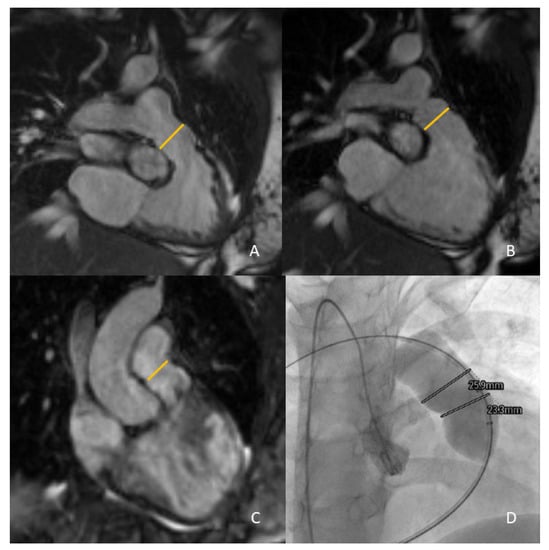

- Goreczny, S.; Dryzek, P.; Moszura, T.; Lukaszewski, M.; Podgorski, M.; Nordmeyer, S.; Kuehne, T.; Berger, F.; Schubert, S. Magnetic resonance and computed tomography imaging fusion for live guidance of percutaneous pulmonary valve implantation. Postep. Kardiol. Interwencyjnej 2018, 14, 413–421. [Google Scholar] [CrossRef]